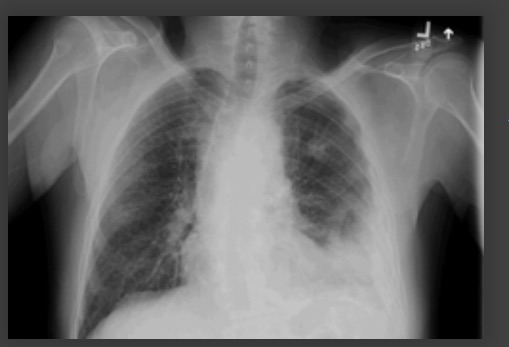

Cavitación – la tomografía computarizada ayuda a identificar diagnósticos alternativos como tuberculosis, cáncer de pulmón, infarto pulmonar, émbolos pulmonares sépticos, ampollas infectadas, absceso pulmonar[Figure caption and citation for the preceding image starts]: Radiografía de tórax que muestra neumonía cavitante en el lóbulo superior izquierdoDe la colección del Dr. Jonathan Bennett. Usado con autorización [Citation ends].